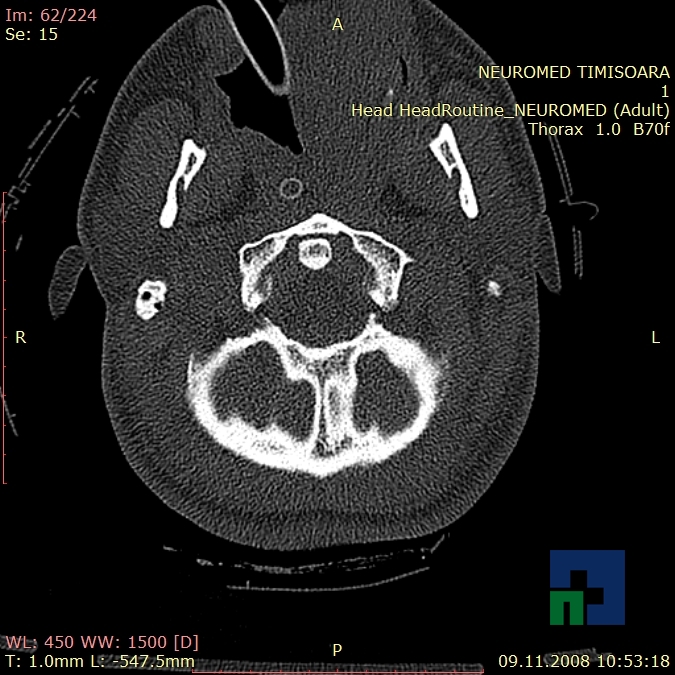

În cazul traumatismelor cranio-cerebrale:

- Diagnosticul edemului cerebral, a contuziei cerebrale, a leziunilor axonale difuze edematoase/hemoragice, a dilacerării cerebrale, a hematomului intraparenchimatos posttraumatic, a hematoamelor subdurale/extradurale (acute, subacute, cronice), a hemoragiei intraventriculare, a hemoragiei subarahnoidiene

- Diagnosticul traumatismelor de bază de craniu

- Diagnosticul fracturilor:

-

- Unice

- Multiple

- Cu înfundare

- Complexe cranio-sinusale

- Complexe cranio-etmoidale

- Complexe cranio-orbitare

- Complexe cranio-faciale